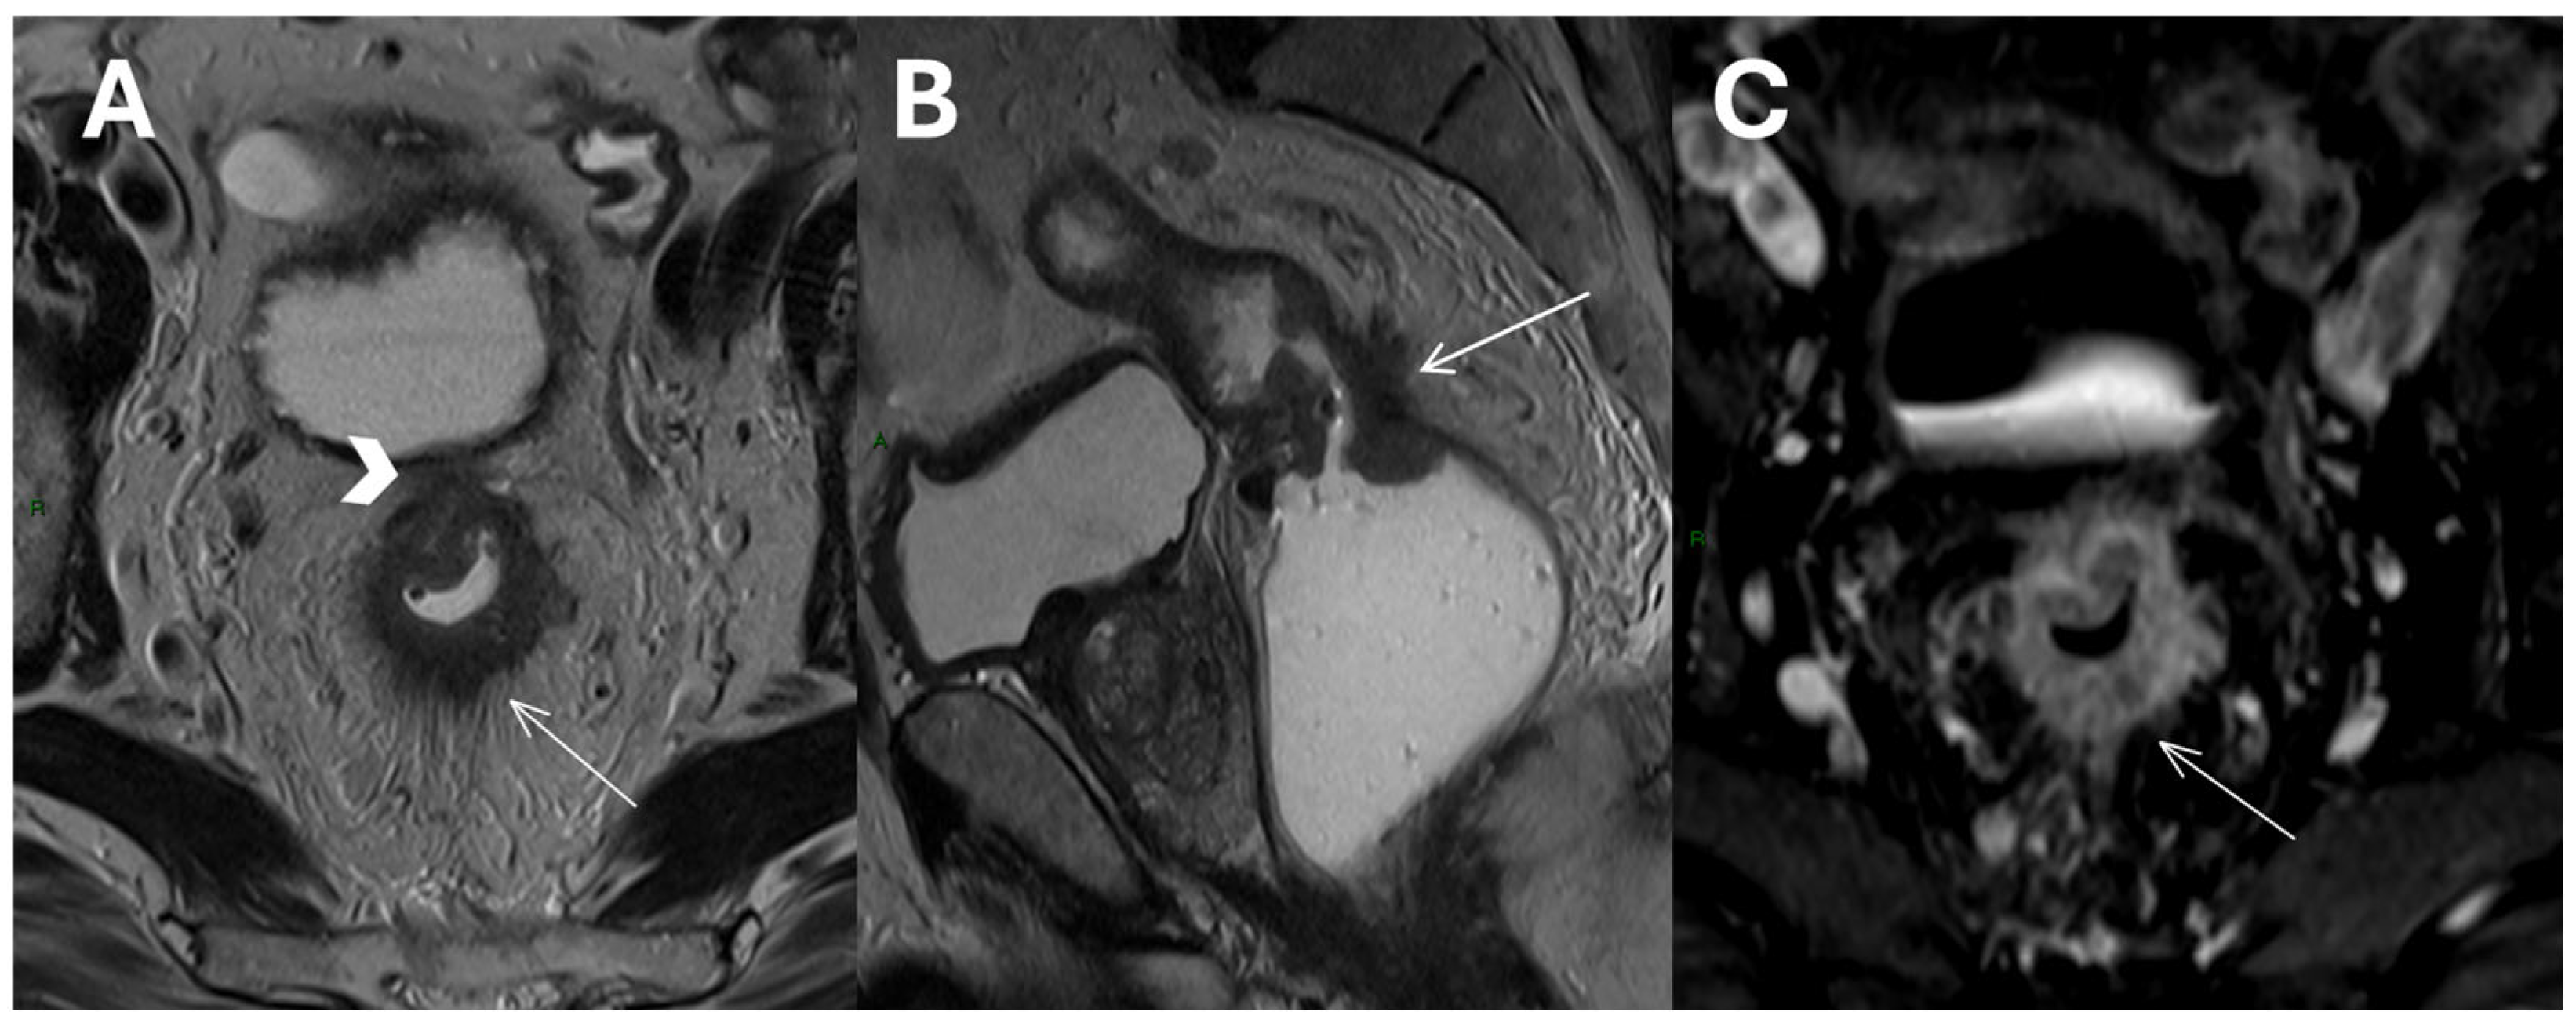

- Complexities of sphincter involvement: Our analysis revealed that sphincter involvement is strongly associated with heightened postoperative complications. This correlation, while not reaching traditional levels of statistical significance, suggests a complexity in surgical approaches when the sphincter is affected. It highlights the need for careful surgical planning and possibly more conservative approaches to preserve sphincter function and reduce complications. The significance of these findings emphasizes the importance of preoperative imaging reviews to better prepare for the challenges that may arise during and after surgery. There remains ambiguity regarding the management of low rectal cancers that affect the anal sphincter complex and the precise delineation, determining their classification as T4b [35]. The Society of Abdominal Radiology’s Colorectal and Anal Cancer Disease-Focused Panel recommends detailed description of anal involvement, specifying the location and length of sphincter muscle affected. This includes identifying involvement of the internal anal sphincter (IAS), intersphincteric space (ISS), or external anal sphincter (EAS) [36]. ESGAR aligns with this detailed approach, advising in detail the involvement of IAS, ISS, and EAS, along with specifying whether the tumor affects the proximal, middle, or lower third of the sphincter complex, and observing any pelvic floor involvement [10]. Providing comprehensive information about sphincter involvement plays a crucial role in the case-by-case decision-making process for patient management, aligning with multidisciplinary team recommendations.

- Lymph node involvement and surgical risk: Notably, our study identifies lymph node involvement as a predictive factor for postoperative bleeding. Lymph node involvement is a crucial prognostic factor in rectal cancer, making preoperative neoadjuvant therapy recommended for these patients to help lower the risk of local recurrence [11,43]. Although MRI is the gold standard for staging, it is less accurate for N staging compared to T staging, with sensitivity and specificity ranging from 58 to 77% and 62 to 74%, respectively [44,45,46]. Other imaging methods, such as computed tomography, have demonstrated similar diagnostic accuracy [47]. Our data suggest that the presence of nodal disease, which indicates a more invasive tumor, may require more delicate and extensive surgical interventions, potentially increasing the risk of bleeding. This insight should encourage surgeons to consider preoperative strategies to minimize this risk, such as advanced surgical techniques or preoperative interventions (Figure 3).